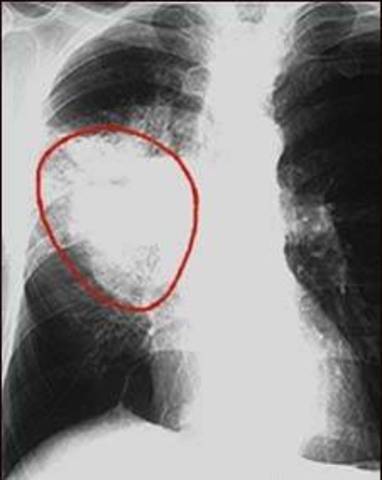

In the early 20th century, leukaemia was considered an incurable, chronic disease. Around 1900, after the discovery of radiation, studies showed that x-rays could reduce the size of tumors.